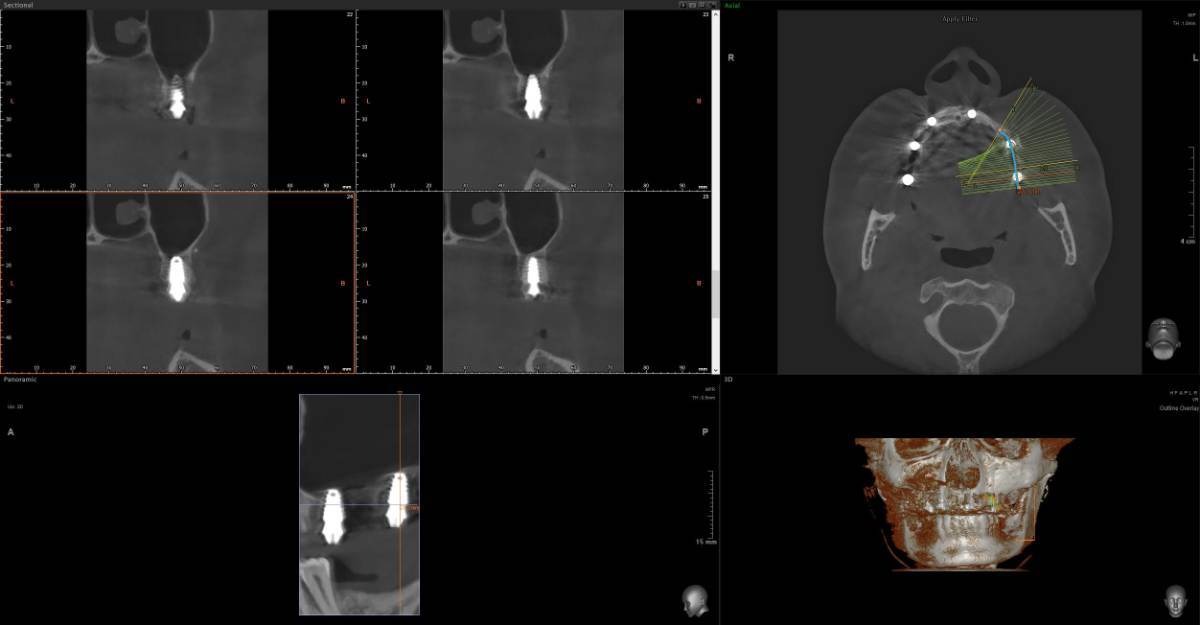

Добрый день. Зубы проблемные с детства очень сильно Полтора-два года назад предварительно удалось спасти не спасаемое, 26 и 27, по крайней мере по нескольких кт перидически, неплохой регресс и заживление костной ткани, даже в области 26 где было большое поражение фуркации, сейчас намного меньше, они не болят уже почти год, до этого очень долго болели даже после качественного лечения и врачи прогнозов не давали конечно же между 24-26 (25 нет уже лет 10) стоит адегизивный бабочка, уже не в самом лучшем состоянии, вернее зубы 24 26 не в очень хорошем, так вот я хотел снять бабочку и одеть на 24-26 металлокерамику, во рту есть несколько металлокерамик единичных, на 3 еще не ставил Есть вариант, и я послушал разных докторов, что можно было бы например 24 просто сделать реставрацию качественно, 26 там без вариантов покрыть коронкой единичной, а 25 имплантат, но я пока избегаю всего так сказать инвазивного, хотя бы еще полтора-два года, с начала 2024 и по середину 2025 болел очень тяжело, Лонг ковидом, это страшное явление которое врагу не пожелаю, возможно даже кто помнит мои темы что я у себя предполагал сепсис, вот именно у меня был он не в виде усталости какой и тд, что чаще всего, а в форме выраженного иммунодефицита + легкого но стойкого системного воспаления , по типу аутоиммунных реакций, в общем не будем вдаваться в эту тему, к тому же она не изучена еще, все только предстоит, спасибо лишь тем докторам-интузиастам, которые просто из спортивного интереса не забросили эту тему и занимаются исследованиями, при разных НИИ, в итоге они меня спасли, помогли определенные противовирусные на длительной основе поставить меня на ноги, что еще раз и том числе мой пример подтверждает вирусный генез Лонга, 1,5 жизни просто выпало у меня Ладно, я далеко ушел уже от темы, я к тому, что более современно наверное считается имплантат и 24 и 26 по отдельности, но повторюсь я боюсь пока лишних инвазивных процедур. Подскажите пожалуйста, каковы минусы моста с металлокерамики на 3 зуба, по каким причинам это считается прошлый век, и какие нюансы меня могут ждать ? Даже если те зубы я рано или поздно потеряю, но даже 3-4 года выиграть еще перед имплантацией, это все равно выигрыш Возможно я думал тот же мост на 3 но из циркония, но тоже не знаю, зубы те хоть и с положительной динамикой но сколько они еще простоят, а цирконий как никак в 2 раза дороже металлокерамики, но если лучше его, тогда рассмотрю -